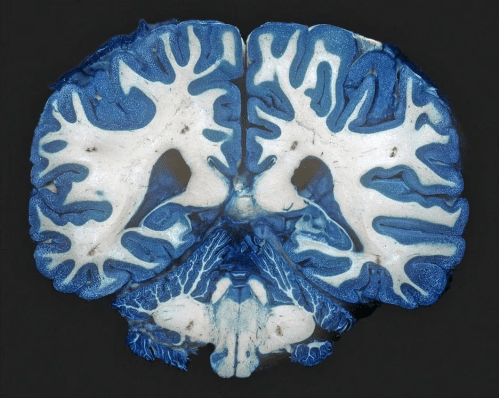

Diferenças nos genes de uma pessoa podem predispô-la à depressão; o mesmo acontece com as diferenças na fiação neural e na estrutura de seu cérebro. Vários estudos mostraram que os indivíduos diferem em como seus neurônios se interconectam para formar vias funcionais e que essas vias influenciam a saúde mental.

Em uma conferência recente, a equipe liderada por Jonathan Repple, pesquisador em psiquiatria da Universidade Goethe em Frankfurt, na Alemanha, descreveu como escaneou o cérebro de voluntários com depressão aguda e descobriu que eles diferiam estruturalmente daqueles de um grupo de controle não deprimido. Por exemplo, pessoas com depressão mostraram menos conexões dentro da “substância branca” das fibras nervosas de seus cérebros. (No entanto, Repple observa que não é possível diagnosticar depressão examinando o cérebro de alguém).

Depois que o grupo deprimido passou por seis semanas de tratamento, a equipe de Repple fez outra rodada de exames cerebrais. Desta vez, descobriram que o nível geral de conectividade neural no cérebro dos pacientes deprimidos aumentara à medida que seus sintomas diminuíram. Não parecia importar que tipo de tratamento os pacientes recebiam.

Uma possível explicação para essa alteração é o fenômeno da neuroplasticidade. “Neuroplasticidade significa que o cérebro realmente é capaz de criar novas conexões, mudar sua fiação”, disse Repple. Se a depressão ocorre quando o cérebro tem poucas interconexões ou perde algumas, então aproveitar os efeitos neuroplásticos para aumentar a interconexão pode melhorar o humor da pessoa.